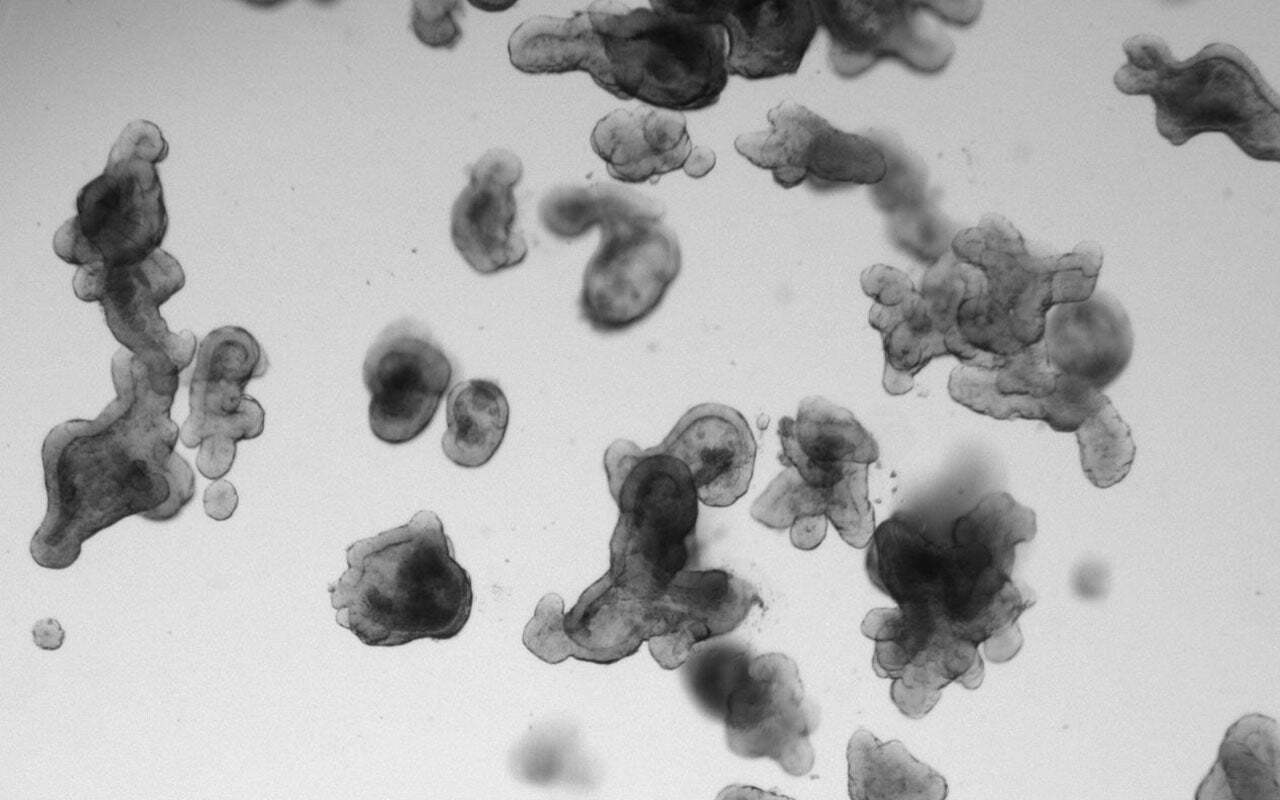

In 2016, two researchers from the University Medical Center Utrecht (UMCU) who approached the disease from different angles started a collaboration to discover new treatment options. Hans Bos had studied RAS signalling for decades and understood the molecular biology behind why these tumours resist treatment. Hugo Snippert had built up expertise and know-how in the new field of patient-derived organoids, which support testing of drug combinations on living tumour tissue. They pooled their knowledge to perform a drug screen on organoids made from the cells of RAS-mutant CRC.

The team wanted to test whether shutting down RAS-mutant signaling with a combination of two classes of drugs, pan-HER and MEK inhibitors, could expose vulnerabilities in these cancer cells. The screen revealed one.

In 23 of 25 organoid models, tumour cells were killed when a third drug was added to the mix: a microtubule-targeting agent1,2. The combination was critical. Dual pan-HER and MEK inhibition only stalled tumour cell growth. The addition of the third drug made cells die. This looked like a lead worth pursuing, especially since microtubule-targeting agents are relatively commonly used chemotherapeutics.

We designed a dose-escalation study to find a safe regimen, followed by a two-stage evaluation of tumour responses. Organoids were not only the scientific rationale for the trial; they were also built into the study design. To better understand participating patients’ drug responses, we collected biopsies, grew organoid cultures from them, and tested drug sensitivity ex vivo alongside monitoring clinical response.

Another key insight came after the trial. The organoids used in the original drug screen were derived from chemotherapy-naïve tumours, whereas early-phase trials typically enroll heavily pretreated patients. When we generated tumour organoids from patients who had participated in RASTRIC, they were much more therapy-resistant than organoids used in the original screen. This suggests that organoids recapitulate therapy-induced resistance, and that if we would have had access to organoids from pre-treated patients earlier in development, we may have seen the limited efficacy of the triple therapy earlier. Then we could have chosen a different drug combination or patient population. This work is ongoing and will be reported separately.